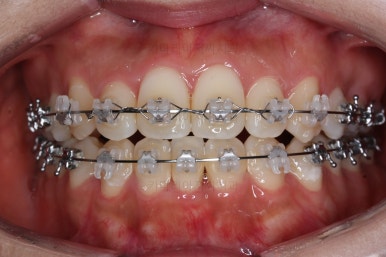

초진 시 입안의 모습입니다.

그냥 봐도 뭔가 애매함이 있죠?

중앙선이 맞지 않고, 교합이 떠보이는 양상이네요.